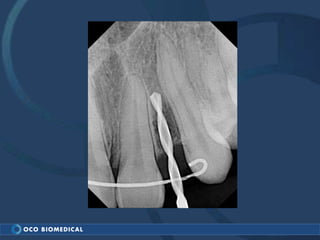

A 3.0mm dental implant was placed to replace congenitally missing maxillary lateral incisors. Dr. Tim Kosinski used a 1.8mm pilot bur and tissue punch to prepare the osteotomy site, then placed the implant by hand and seated it with a torque wrench. After ensuring the implant trajectory was within the restorative envelope, an acrylic coping was placed for temporary fabrication. At the 1 week post-op appointment, excellent soft tissue response and papilla formation were observed, and a final impression was taken to send to the lab for crown fabrication.